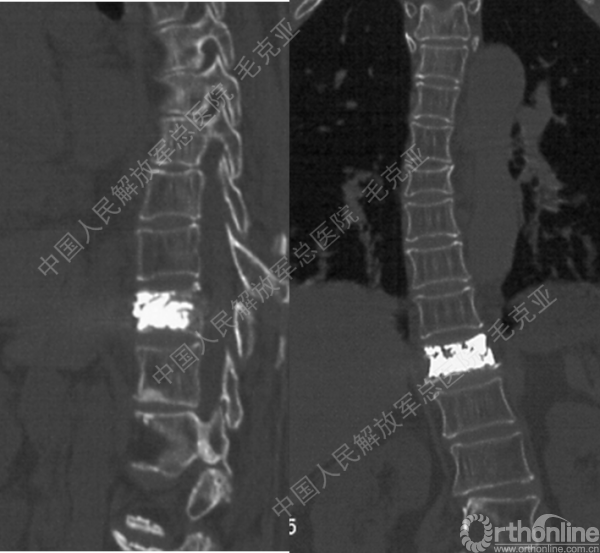

导语:随着社会老龄化的不断加速,骨质疏松性椎体压缩骨折作为一种普遍存在的老年骨科疾病已经成为现今骨科界的一个热点话题。传统的保守疗法治疗效果不佳,而现有的椎体增强技术又具有多种风险和缺陷。针对这种现状,中国人民解放军总医院毛克亚教授提供了一种新的解决方法。